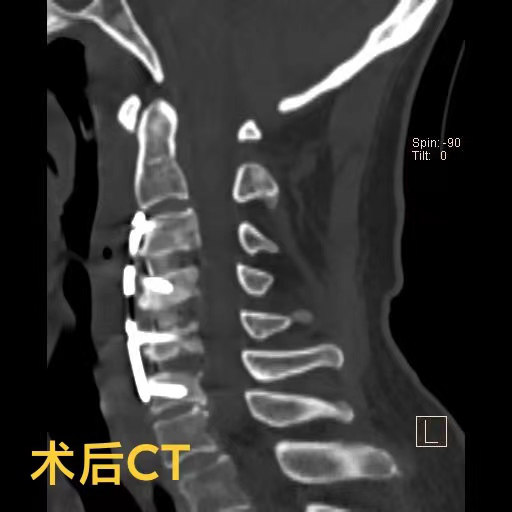

【厚德精醫】多年頑疾一朝除!神經外科為老人矯正嚴重頸椎變形

近日,74歲的陳爺爺,由于出現頸部疼痛、手腳麻木、行走困難等癥狀被家人送到重慶醫科大學附屬璧山醫院(重慶市璧山區人民醫院)康復醫學科就診??剖伊_秋紅主治醫師為其進行了頸椎核磁共振檢查,結果提示,患者頸椎變形已導致脊髓神經受壓,隨時有高位截癱的風險。陳爺爺患有頸椎病多年,因擔心手術帶來的風險,長期依靠理療來緩解病痛,這次也是因為癥狀日趨嚴重,無奈之下才前來就醫。

羅醫生第一時間聯系了神經外科脊柱脊髓組的鄧雷主治醫師。針對陳爺爺及其家屬的擔憂,鄧雷主治醫師進行了耐心細致的溝通,最終陳爺爺決定配合醫護進行手術治療。患者高齡且有基礎疾病,手術方案需要慎之又慎。神經外科副主任(主持工作)徐忠燁主任醫師組織全科醫生根據患者具體病情,制定了最終方案:前路3節段頸椎間盤切除+頸椎后凸畸形矯正。

陳爺爺長期的頸椎變形產生了大量骨質增生,給術中的鄧雷、蔣登志醫生出了難題。在神經顯微鏡下,他們的眼睛如鷹,指尖之中飛舞最溫柔的神經刀鋒,雕塑著最堅硬的頸椎驁骨。最終,手術耗時兩個半小時,成功矯正,沒有神經損傷!患者術后3天康復出院。